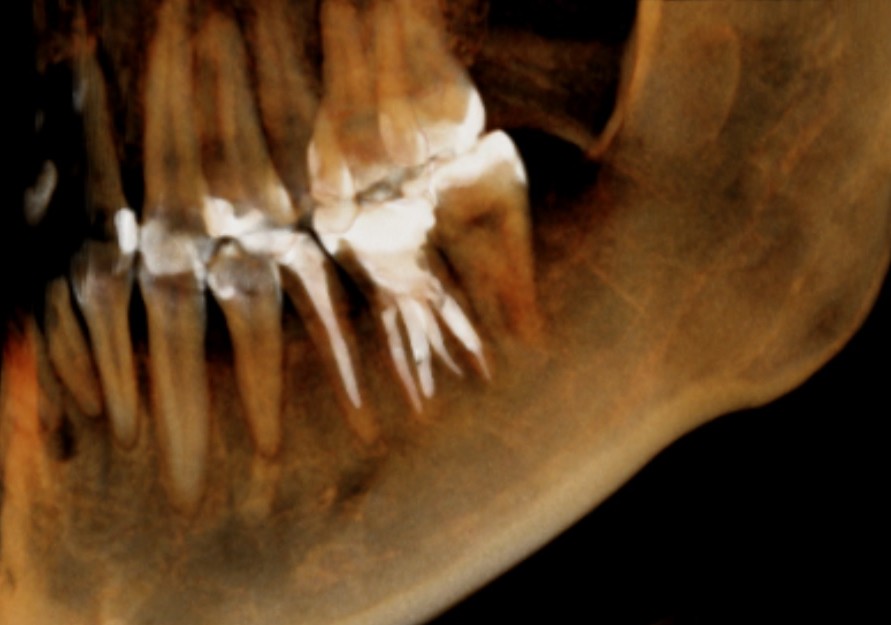

CT撮影です。

下の6番目の歯で、2本の根があります。

それぞれの根の先に黒い影があります。根の先で膿んで顎の骨が溶けています。

CTの3D画像で確認してみましょう。